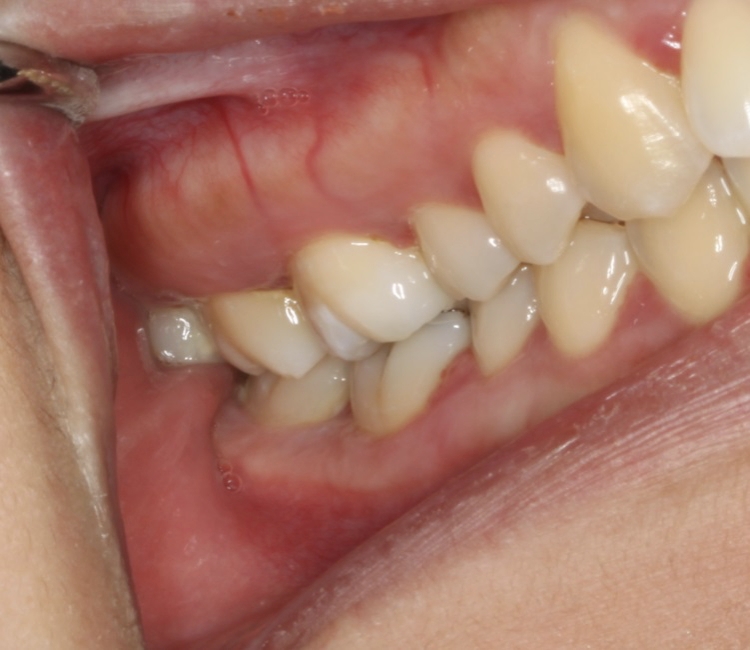

Wisdom teeth or third molars are the last teeth to come into the mouth. They emerge in your mouth from ages 15-21. When a tooth doesn’t fully emerge properly and is stuck under the gums or bone, then it is called “impacted.” Impacted wisdom teeth can cause issues as they try to come in, including infection and pain. They can also affect the health of your second molars.

We recommend wisdom teeth be removed in adolescents (ages 15 to 21) in order to prevent future problems from occurring. Occasionally, they are removed earlier if they are impeding the normal emergence of the second molars. Typically, wisdom teeth are easier and safer to remove when they are partially formed. As they grow longer and your jaw bone becomes denser with age, then their removal can be more traumatic, and have more risk, thus increasing the chances for complications.